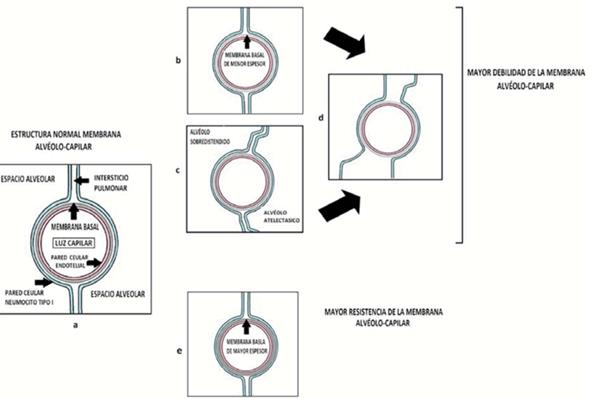

La membrana alvéolo-capilar posee una gran resistencia que le permite hacer frente a una amplia variedad de situaciones fisiológicas y patológicas. Dicha resistencia está dada por la membrana basal conformada básicamente por colágeno tipo IV dispuesto como una malla entre la célula endotelial y el neumocito tipo I. A esto se suma el soporte generado por el intersticio pulmonar y la disposición alveolar, estableciendo un sistema de sostén capilar (Figura 2a)3,4.

Figura 2: Se esquematizan los componentes básicos de la membrana alvéolo-capilar. (a). Debilitamiento de la resistencia de la membrana alvéolo-capilar por menor espesor de membrana basal (b), o pérdida del sostén capilar generado por los alvéolos y el interticio pulmonar (c), o combinación de ambos en el pulmón prematuro (d). Como contrapartida un mayor espesor de la membrana basal incrementa la resistencia de dicha membrana (d).

Ante una lesión directa de la membrana basal se produce sangrado pulmonar, como ocurre en la enfermedad de Good Pasture (ataque directo al colágeno tipo IV), lo que deja en evidencia la importancia de dicha membrana y en especial la malla de colageno tipo IV4,5.

La membrana basal es producida por las células endoteliales y los neumocitos tipo I, las cuales constantemente están monitorizando el estrés parietal capilar. Está descripto que en pacientes con estenosis mitral la membrana basal tiene mayor espesor para contrarrestar el incremento estés parietal generado por la hipertensión veno-capilar (Figura 2e). Es plausible pensar que en situaciones donde la presión capilar se encuentra disminuida ocurra el fenómeno inverso, debilitamiento de la membrana basal y por ende la membrana alvéolo-capilar (Figura 2b)3.

En este contexto, el factor prematurez con la consiguiente inmadurez pulmonar (etapa alveolo-sacular) determina una especial fragilidad de la membrana alvéolo-capilar , ya que a una membrana basal mas débil se suma un déficit en el sostén capilar dado por una inadecuada estructura alveolar e intersticial (Figura 2d). Ésta fue la base para el desarrollo de sangrado alveolar ocurrido en el caso 12.

La presencia de unidades alveolares atelectasicas o sobre distendidas determina pérdida del sistema de sostén capilar generado por la disposición alveolar y el intersticio pulmonar, situación que favorecería la falla por estrés (Figura 2c)2.